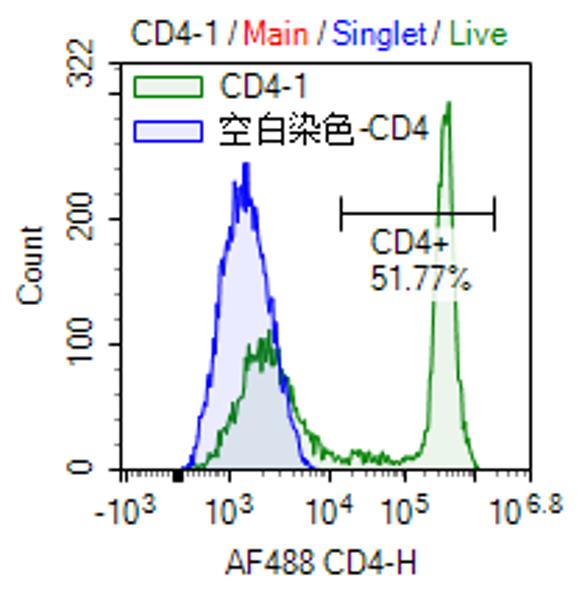

Product Image